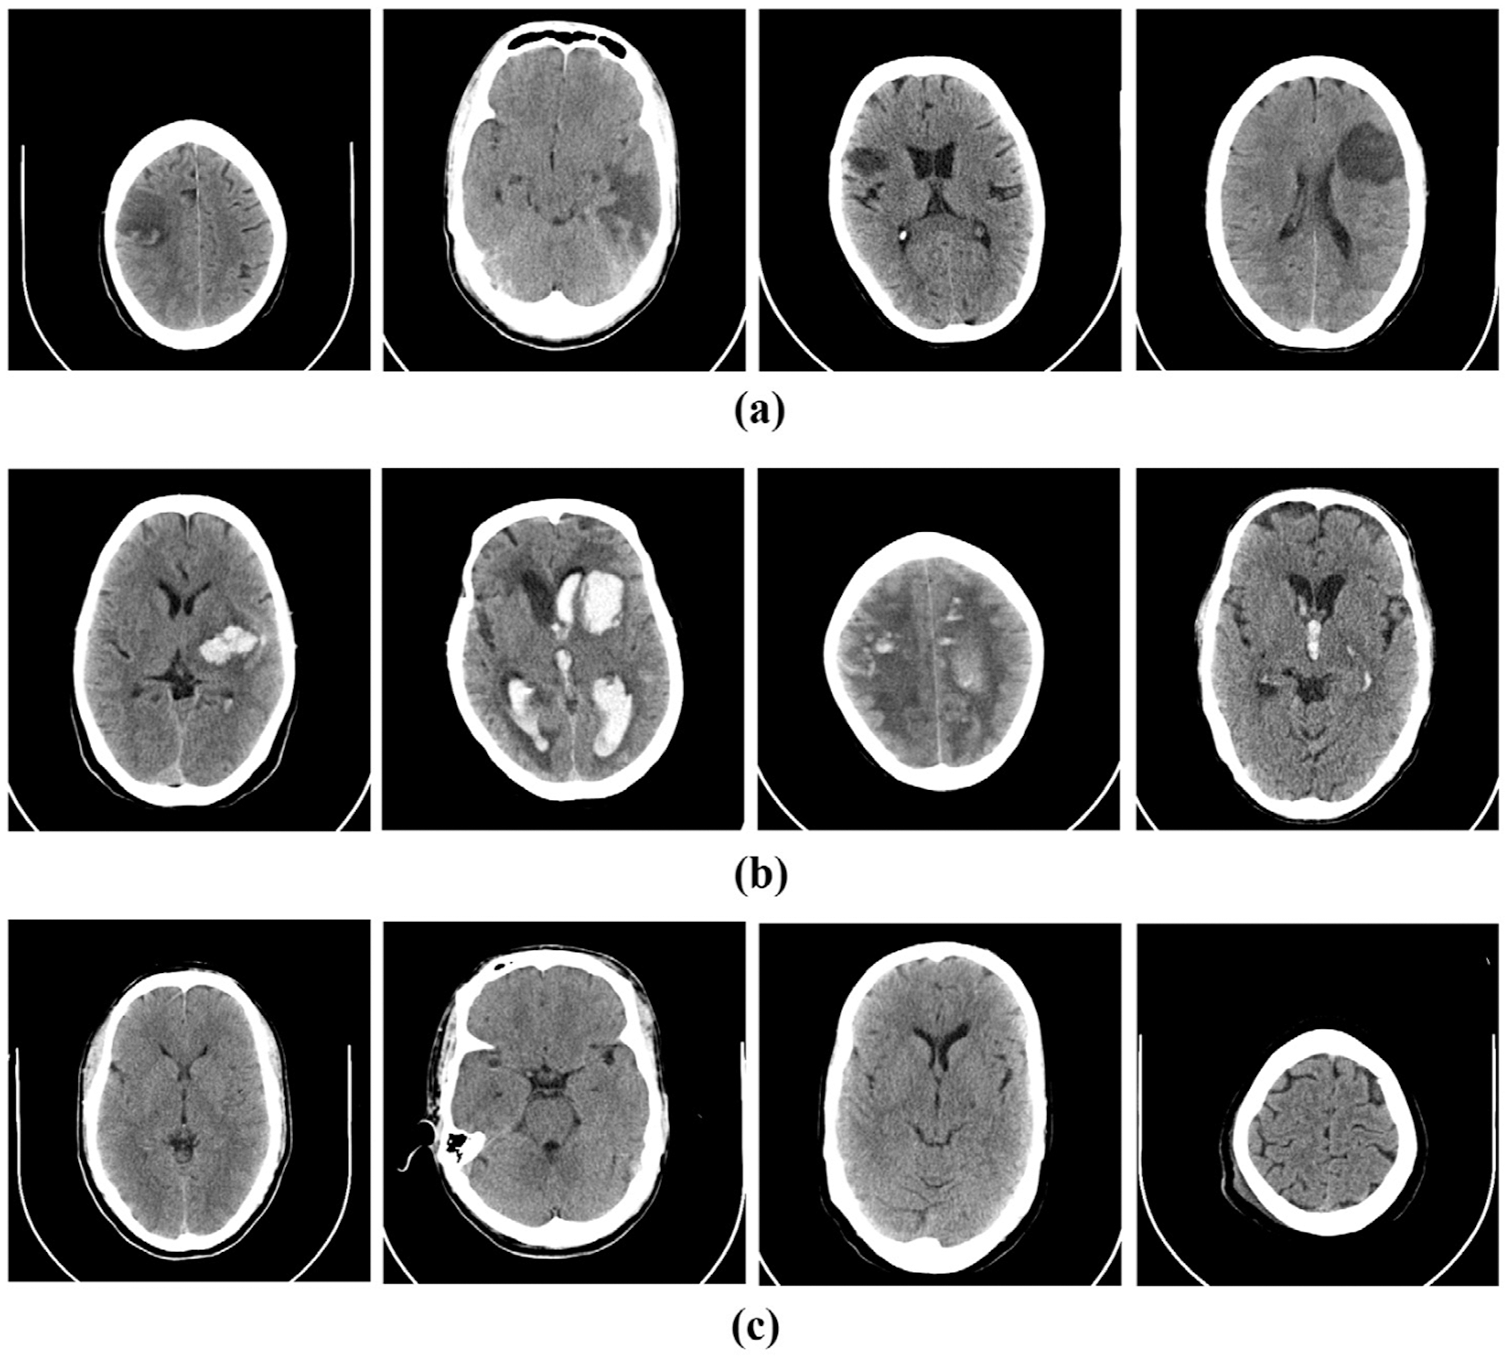

The following section presents an automated classification approach for predicting the category to which the brain CT scan belongs, including images in the hemorrhagic, ischemic, and healthy categories. Hemorrhagic stroke results from a ruptured occluded blood vessel in the brain that seeps into the surrounding tissue. Hypertension, trauma, aberrant blood vessels, circulatory disorders, aneurysms, and cocaine use are the most common causes of hemorrhagic stroke. Ischemic stroke, on the other hand, occurs when blood flow to the brain is stopped due to the presence of a blood clot or can also lead to life-threatening consequences in the form of cerebral hemorrhage [17]. Fig. 1 shows examples of the two types of strokes and healthy brain images.

Figure 1: Sample CT images of (a) ischemic, (b) hemorrhagic stroke and (c) normal brain